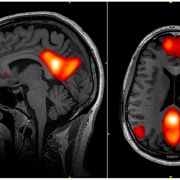

Default Mode Network

The default mode network (DMN) is a system of connected brain areas that show increased activity when a person is not focused on what is happening around them. The DMN is especially active, research shows, when one engages in introspective activities such as daydreaming, contemplating the past or the future, or thinking about the perspective of another person. Unfettered daydreaming can often lead to creativity. The default mode network is also active when a person is awake. However, in a resting state, when a person is not engaged in any demanding, externally oriented mental task, the mind shifts into “default.”

The default mode network is about self-focus and mental time-travel, and its inactivity appears to be related to varied forms of mental illness. The DMN is involved in episodic memory processing, with introspection and autobiographic memory as important cognitive processes. Researchers have reported dysregulation between the components of the default mode network in patients with Alzheimer’s disease as well as those with Parkinson’s disease, illnesses that affect memory processing.

Connectivity between particular default mode network areas of the brain has been linked to higher levels of rumination in depressed individuals. The depressive among us ruminate about their regrets, failures, shame, and anger. Further links with default mode network dysregulation have been made to autism, schizophrenia, and other conditions.

The default mode network, discovered by neurologist Marcus Raichle, spans a number of brain regions, incorporating parts of the prefrontal, parietal, and temporal cortices that show joint activation, or deactivation, in connection with particular mental functions. It is one of a number of such brain networks, which also include the salience network and the executive control network.